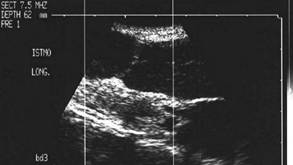

Lob drept , proiectie longitudinala si trasversala .

Barbat de 44 ani. Nodul mare in lobul drept si istm de 31x44x44mm, (30 cc) cu contur net, hipoecogen, neomogen, cu macrocalcificare.

Examn citologic: neoplazie oncocitara (a c. Hurthle).

Examen histologic postoperator: adenom cu celule Hurthle.